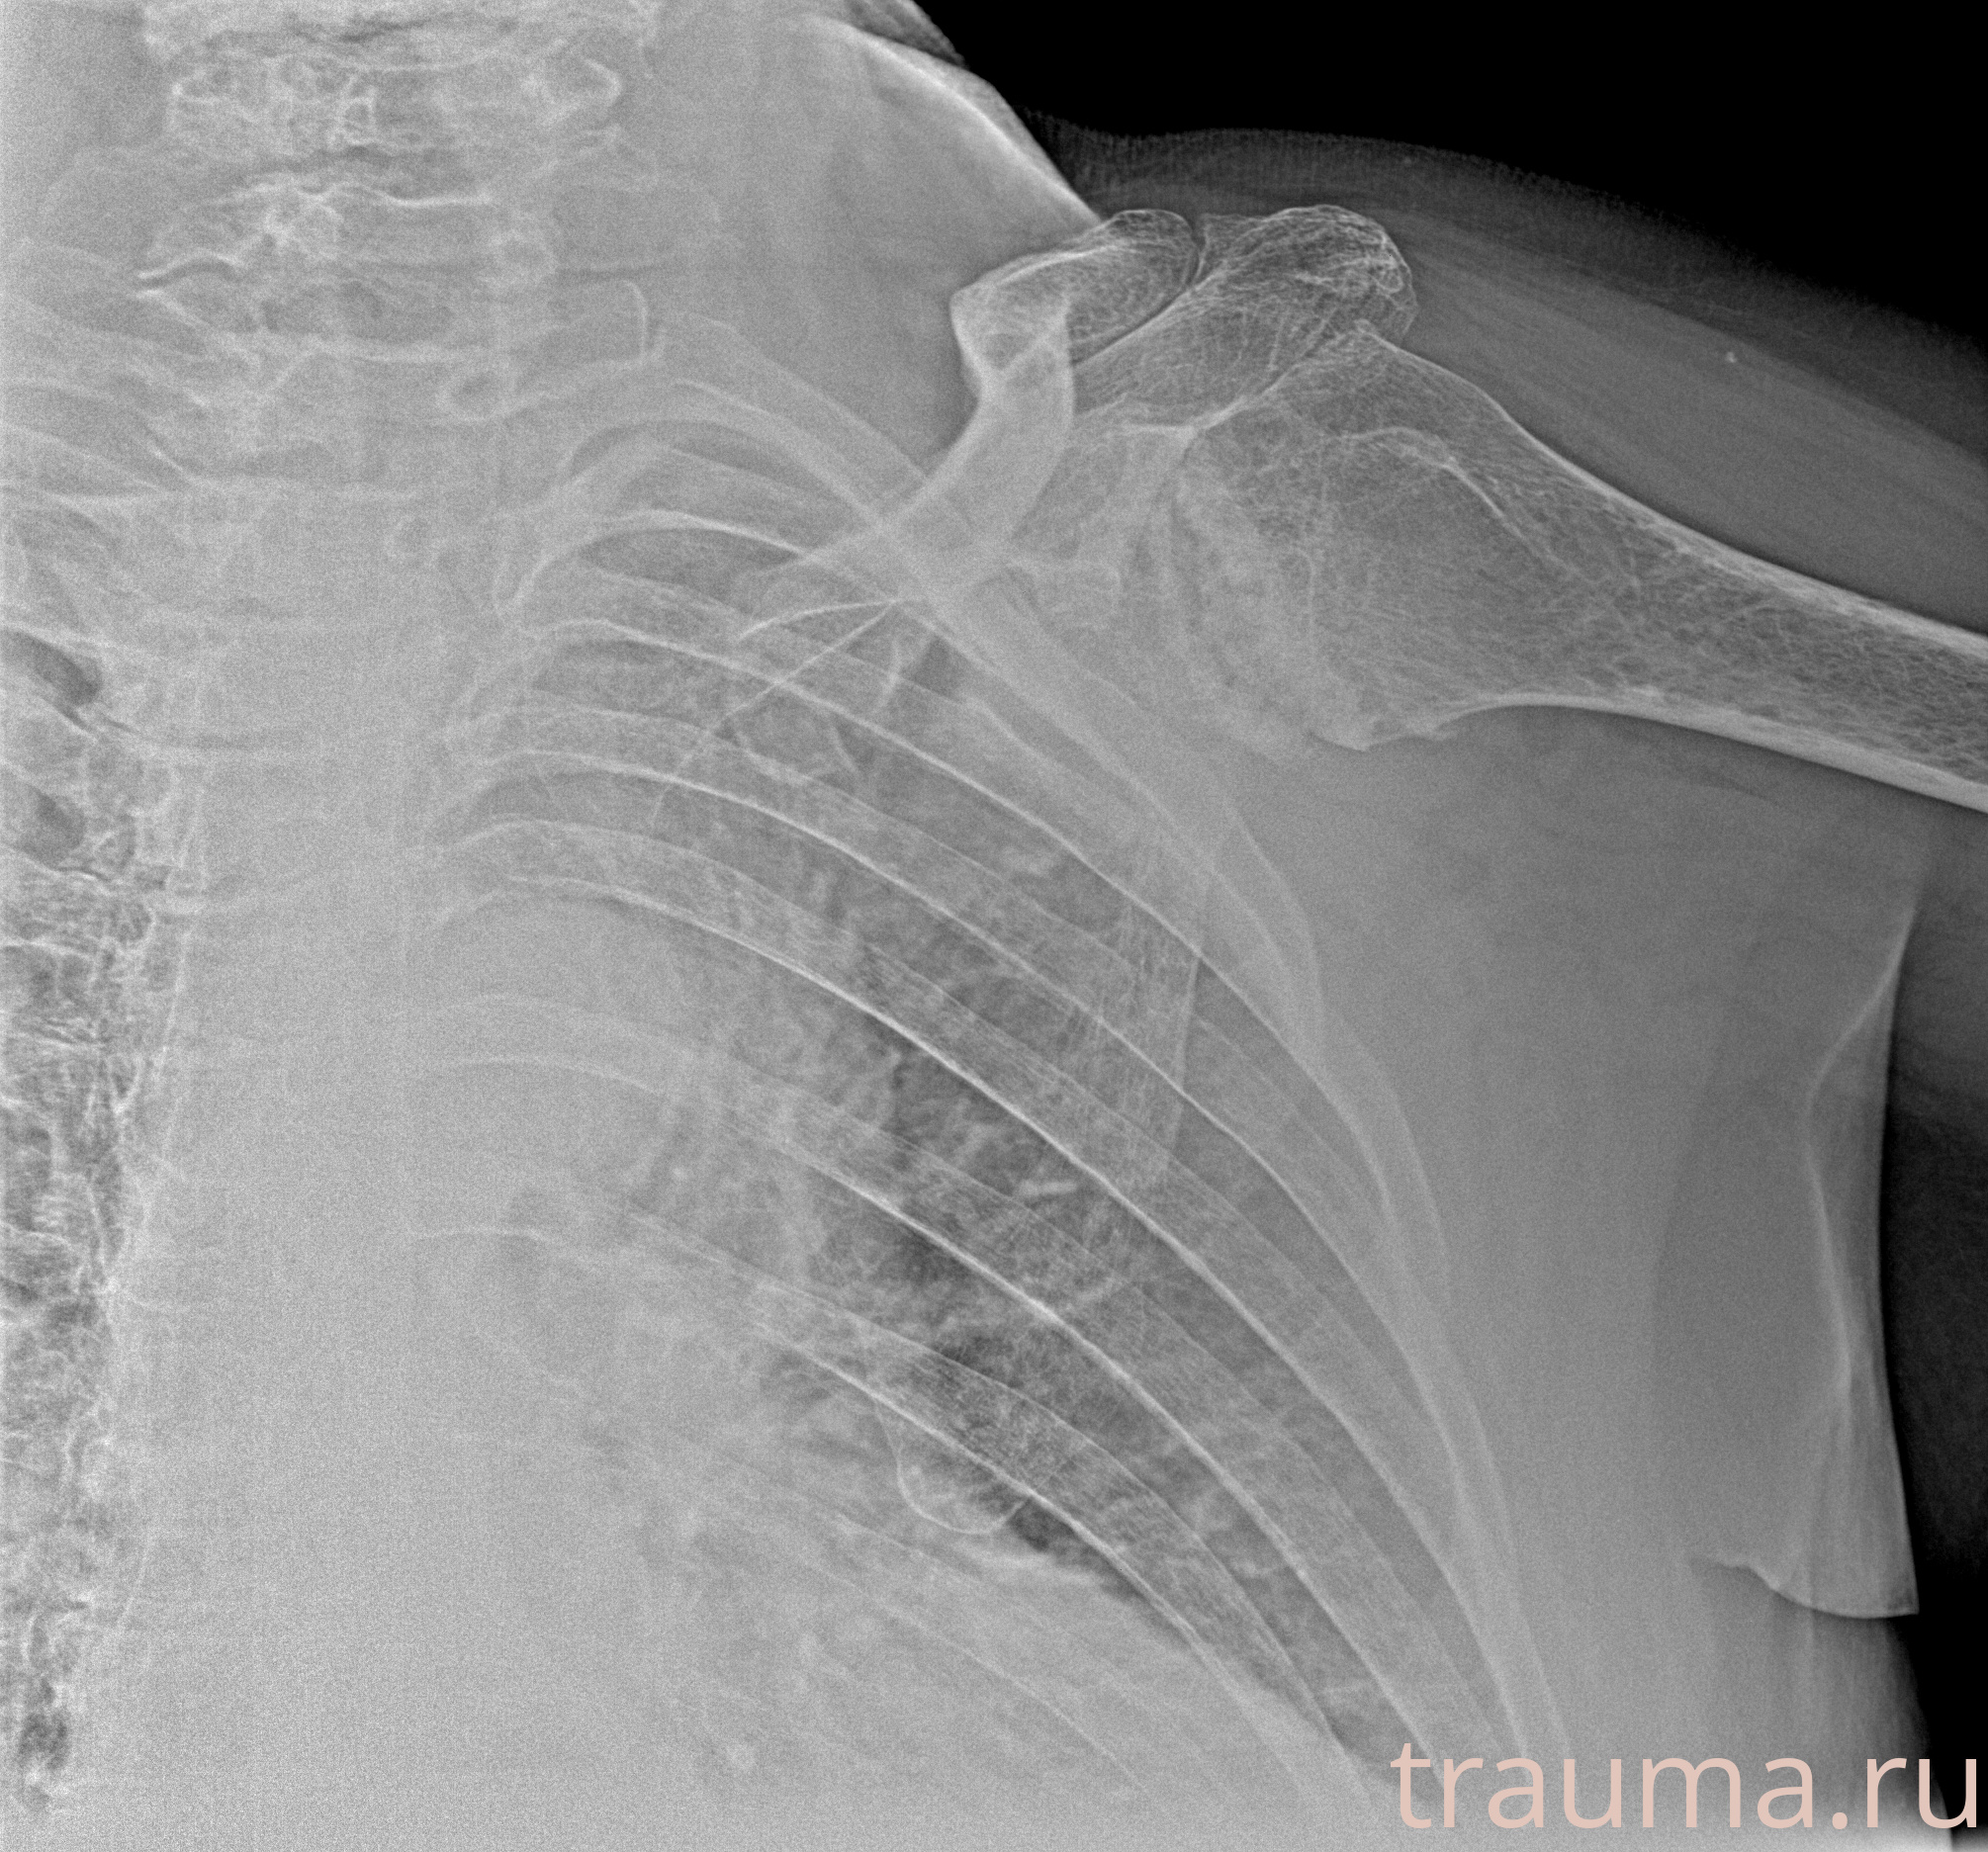

Рентгенограммы

Рентген на дому: по вашему адресу приезжает врач-рентгенолог, травматолог-ортопед с мобильным рентгеновским аппаратом, проводит диагностику травмы или заболевания, делает необходимые рентгенограммы, дает рекомендации по дальнейшему лечению. Получить качественные снимки в домашних условиях возможно благодаря уникальной методике, разработанной МосРентген Центром для института  Склифосовского